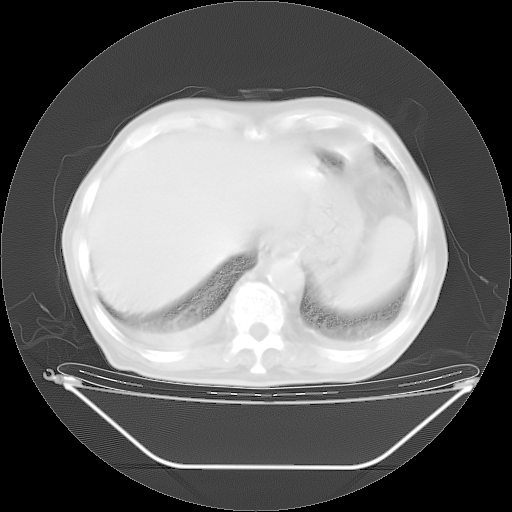

今天复查肺部CT,发现双肺广泛磨玻璃样改变。所以我把3月19日和5月9日相隔50天的肺部CT上传。请大家会诊。

5月9日肺部CT(在4月27日齐鲁医院肺部CT描述部分肺组织磨玻璃样改变,12天后肺组织广泛磨玻璃样改变)

2009年5月9日肺部CT

大致读了系列胸部CT:纵隔窗无明显异常,肺窗:从4、27至今:主要是双肺中下野外带可见毛玻璃样改变,目前处于急性肺泡炎阶段,至于原因考虑1、结替组织或胶原血管性疾病所致?2、恶性疾病如恶组在肺部所致的表现或细支气管肺泡癌?3、药物或其它原因如肺蛋白沉着症所致肺泡炎目前不太可能?总之,明天就去请我院的呼吸科、感染科、血液科和临免专家会诊哈。